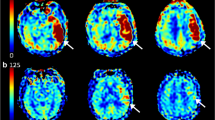

The vast majority of international reports on predicting CHS after MMD by ICG-FLOW800 video angiography currently place the selection of the ROI on the surgically anastomosed MCA and other surrounding thicker vessels20,26. In this study, we shifted the ROI selection target to the microvasculature. We refer to the terminal branches of the vessels surrounding the receptor arteries in a small area as “small regional microvasculature” (SRMV) (Fig. 1). Our objectives were to assess the hemodynamic changes in the peri-anastomotic MCA and SRMV before and after bypass surgery using ICG-FLOW800 video angiography, to verify whether the hemodynamic changes in SRMV could be used as a predictor of CHS after direct hemodynamic reconstruction for MMD, and to calculate and compare the diagnostic accuracy of the MCA and SRMV for predicting CHS separately.

Comparisons were made between the hemodynamic data from the SRMV and MCA groups, as well as the CHS and non-CHS groups (Figs. 2 and 3). In the SRMV group, the values of the hemodynamic parameters were as follows: ΔCBF, 86.99% ± 50.03%; ΔTTP1/2, − 28.07% ± 35.16%; and ΔCBV, 67.82% ± 34.14%. In the MCA group, the values of the hemodynamic parameters were as follows: ΔCBF, 54.61% ± 42.73%; ΔTTP1/2, − 25.58% ± 37.33%; and ΔCBV, 42.69% ± 34.21%. Compared to the MCA group, both ΔCBF and ΔCBV were significantly higher in the SRMV group (p < 0.001) and ΔTTP1/2 was slightly lower (p = 0.061). The hemodynamic parameter values in the SRMV for the CHS group were as follows: ΔCBF, 119.51% ± 45.66%; ΔTTP1/2, − 36.46% ± 28.98%; and ΔCBV, 87.89% ± 33.62%. Similarly, the values of the hemodynamic parameters in the MCA were as follows: ΔCBF, 77.69% ± 45.09%; ΔTTP1/2, − 33.56% ± 30.72%; and ΔCBV, 65.59% ± 29.48%. The hemodynamic parameter values in the SRMV for the non-CHS group were as follows: ΔCBF, 59.62% ± 35.48%; ΔTTP1/2, − 21.01% ± 38.98%; and ΔCBV, 50.91% ± 24.48%. Similarly, the values of the hemodynamic parameters in the MCA were as follows: ΔCBF, 35.17% ± 29.69%; ΔTTP1/2, − 18.85% ± 41.73%; and ΔCBV, 23.41% ± 25.04%. The ΔCBF and ΔCBV were significantly higher in the SRMV and MCA of the CHS group compared to the non-CHS group (p < 0.001), while TTP1/2 was slightly lower (p = 0.199, p = 0.251).

Our hospital received a lady of 51 years who had been experiencing headaches and limb weakness for a year. A preoperative magnetic resonance perfusion imaging examination showed hypoperfusion in the right hemisphere. DSA shows occlusion of the right anterior cerebral arteries (ACA) and MCA with peripheral moyamoya vessel formation. After ruling out any surgical contraindications, a STA-MCA bypass was carried out on the right side. Intraoperatively, ROIs were set at SRMV and MCA by ICG-FLOW800 video angiography, respectively. Analysis of the hemodynamic parameters of the two different ROIs showed that ΔCBF and ΔCBV increased more significantly in SRMV than in MCA. On the second postoperative day, the patient had aphasia. The postoperative magnetic resonance perfusion imaging revealed that right cerebral perfusion had significantly increased since the preoperative period. (Fig. 5).

DSA showed occlusion of the right ACA and MCA with moyamoya vessel formation (A). ASL showed hypoperfusion in the right hemisphere (B). Suitable receptor vessels were selected by ICG-FLOW800 (C). ROIs were set up, and hemodynamic analyses were performed in the SRMV and the thick MCA around the anastomosis, respectively (D,E). ICG-FLOW800 showed good hematologic reconstruction (F). On the second postoperative day, the patient developed aphasia, and the magnetic resonance perfusion imaging showed increased in perfusion compared to the preoperative period (G).